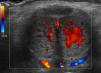

La ecografía Doppler muestra un aumento de la vascularización en la base del cuerpo cavernoso izquierdo (fig. 1). En la arteriografía, se observa la laceración tanto de la arteria peneana izquierda, como de una rama de la arteria obturadora del mismo lado (fig. 2).